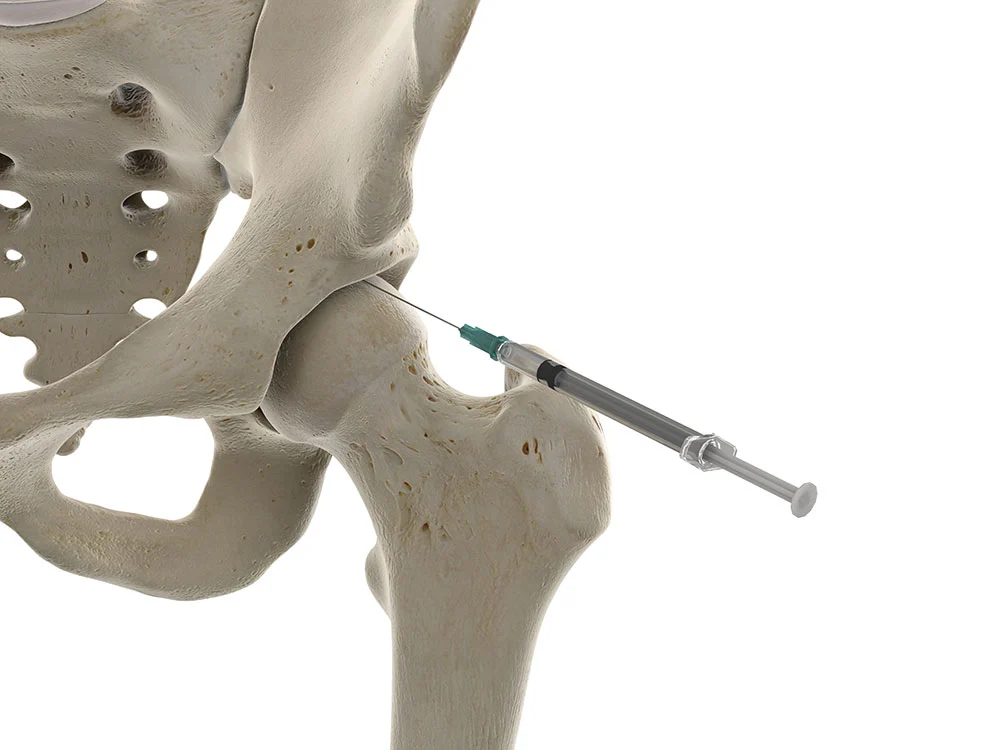

O que é a infiltração do quadril?

É a aplicação de fármacos ou substâncias terapêuticas diretamente na articulação do quadril (intra-articular) ou em estruturas periarticulares (bursas/tendões). Realizamos com ultrassom ou fluoroscopia para aumentar a precisão da agulha, reduzir riscos e melhorar o conforto do paciente.

- Guiada por imagem ( ultrassom ou radioscopia ): maior acurácia que técnicas por marcos anatômicos.